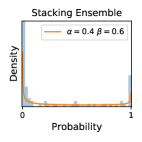

5.1 Distribution of Uncertainty Scores

Distribution of Uncertainty Scores Across Different Severity Levels As explained in Section 3, each uncertainty metric essentially defines an order/ranking among the data points. We conducted an analysis to better understand what data will be assigned high uncertainty under a particular uncertainty metric . Picking out the highest ranked data points (), we calculated the ratio of data points from each SL. Figure 4 summarizes the results as box plots for the Kaggle-DR and the Messidor-2 datasets; additional detailed statistics can be found in Table S.1 in the supplementary materials. From the plot and table, SL1 & SL2 examples account for a higher proportion among the top-ranked uncertain examples across the three ensemble methods. This finding matches our intuition that incipient disease examples (SL1 & SL2) are more likely to be considered uncertain by ensemble methods due to their ambiguity.

Comparing the three ensemble methods in Figure 4, the stacking ensemble method has the highest ratios of SL1 & SL2 data among the high-uncertainty examples it identified under both mean and var. TTA showed slightly better performance than MC-dropout but still falls behind the stacking ensemble method. Considering the fact that SL0 examples accounted for the majority of the dataset, the stacking ensemble method was much more precise (specific) in selecting truly ambiguous data points that were difficult to classify. From Figure 3, we can also see that the stacking ensemble method greatly outperformed the other two methods in finding false negatives under both mean and var uncertainty metrics.

In contrast, the MC-dropout method showed the worst overall performance among the three, as it can be seen from the high ratios of SL0 examples among the uncertain negatives in Figure 4. The histograms in Figure 2 provides another perspective to look into the phenomenon, where a decent proportion of MC-dropout model’s predictions on SL0 inputs entailed low confidence (far from 0 or 1), which from another angle explained why MC-dropout was less specific in terms of lower FNP; many no-DR inputs (i.e. SL0) were erroneously assigned high uncertainty by MC-dropout models.

It is still an open question why the evaluated MC-dropout networks signaled relatively high uncertainty on SL0 & SL3 & SL4 data that are less likely to be ambiguous. We conjecture that much of the “uncertainty” indicated by disagreement among test-time dropout samples actually reflects the stochastic nature of dropout networks rather than the real decision uncertainty associated with the data. It is worth noting that the MC-dropout model we evaluated was not weak per se; they all achieved above Area Under Curve (AUC) scores on test sets. The weakness of individual test-time samples (which explains their low-confidence predictions on SL0 & SL3 & SL4) might have been hidden when they are aggregated into an ensemble—a well-known advantage of ensemble learning. Our results suggested that the uncertainty information given by implicit ensemble methods such as MC-dropout and TTA might not be as reliable as that from explicit ensemble approaches (e.g., stacking ensembles). Similar findings on MC-dropout can be found in some previous papers [1].